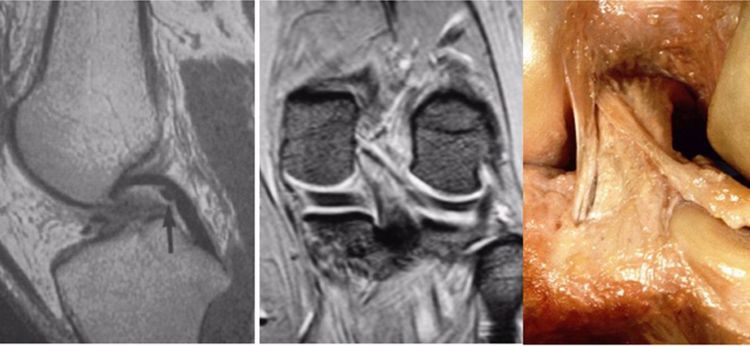

2.撕脱骨折:后交叉韧带胫骨附着点的撕脱骨折较常见。表现为胫骨平台后部有线形的T1加权低信号,T2加权,STIR高信号的骨折线,撕脱的碎片和后交叉韧带相连而韧带的连续性未见中断。

3.后抽屉征:因胫骨后沉引起,除非膝关节脱位,否则后移程度不重。

4.内侧胫骨平台撕脱骨折:胫骨平台前外侧撕脱骨折(Segond骨折)常常合并ACL损伤。而内侧胫骨平台骨折撕脱骨折则常常合并PCL损伤。